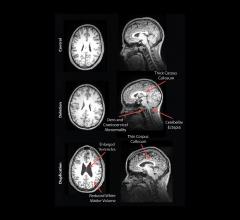

Young hockey players who have suffered concussions may still show changes in the white matter of the brain months after being cleared to return to play, researchers at Western University have found. These findings were achieved through use of sophisticated magnetic resonance imaging (MRI) techniques.